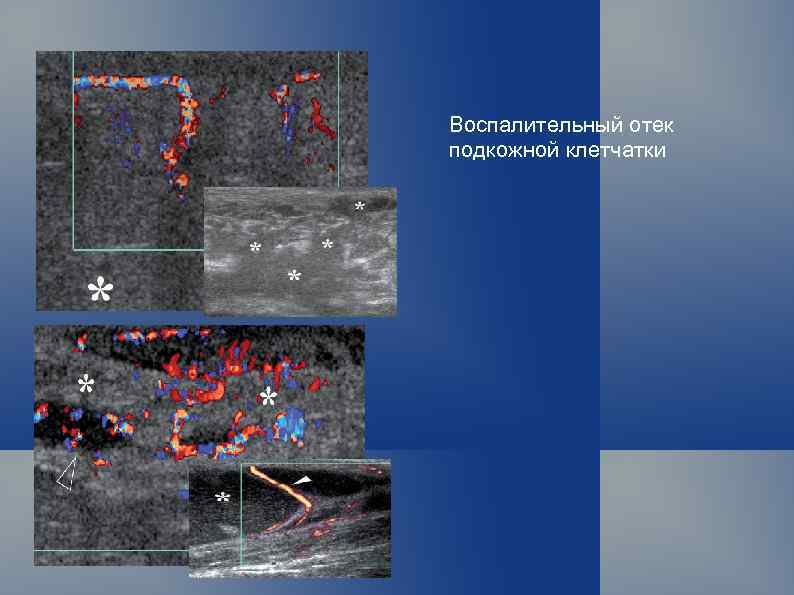

Воспалительный отек подкожной клетчатки